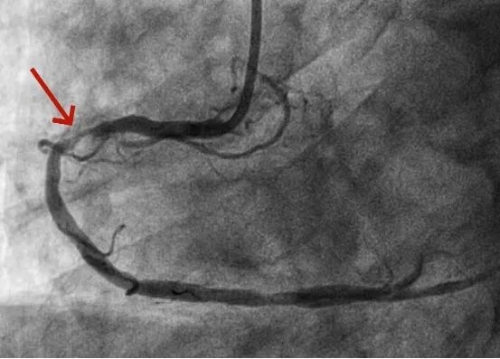

【山好水好人更好】州医院成功抢救七旬东北突发重症游客